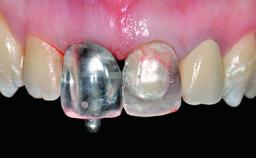

A 32-year-old female Caucasian patient with a compromised maxillary right central incisor was referred to us by a general dentist. Her chief complaints were discomfort and mobility of tooth 11 with unsatisfactory esthetics due to discoloration. The patient reported a previous trauma, some years earlier, as the origin of pathology on the afflicted tooth. Anamnesis was negative for any other dental or periodontal pathology in the remaining dentition. The patient did not take any medication and reported to be a light smoker (5–10 cigs/day). She had high esthetic expectations of her treatment. The extraoral examination revealed a high smile line with full exposure of her maxillary teeth and surrounding soft tissue in the area between the second premolars.

Lip Line No exposure of papillae Exposure of papillae Full exposure of mucosa margin

Periodontal Phenotype Low-scalloped, thick Medium-scalloped, medium-thick High-scalloped, thin